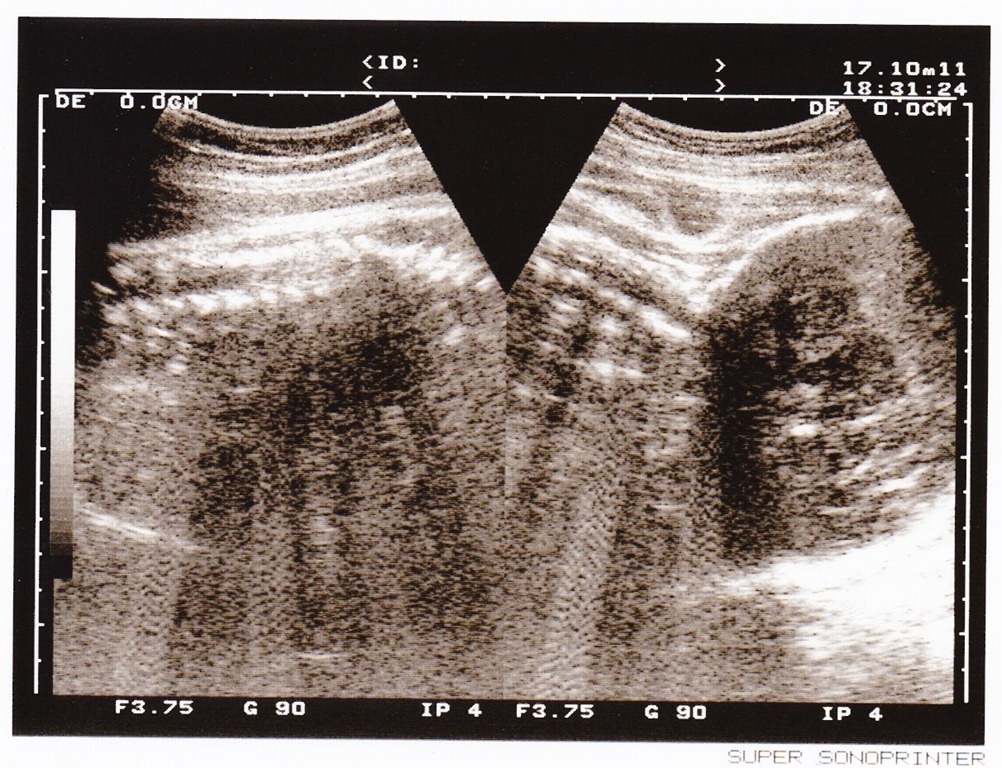

100/8/13 30周大,這時的我胎位轉正了,頭圍31周略大;媽媽因為耐糖檢查超過標準,要再複檢,現在我的胎動已經可以讓媽媽的肚子整個抖動囉~

![]()

100/8/15 30周,今天進行常規性超音波檢查,體重1500g,頭圍31周,肚圍29周大,都正常~側臉拍得好清楚啊,鼻子看起來不太高,上嘴唇跟下嘴唇張開開的。媽媽說這時候的我的手阿腳ㄚ,會在肚皮上鼓起圓圓的一球,從媽媽的肚皮滑動個5cm的距離,再逐漸消失於肚皮表面。